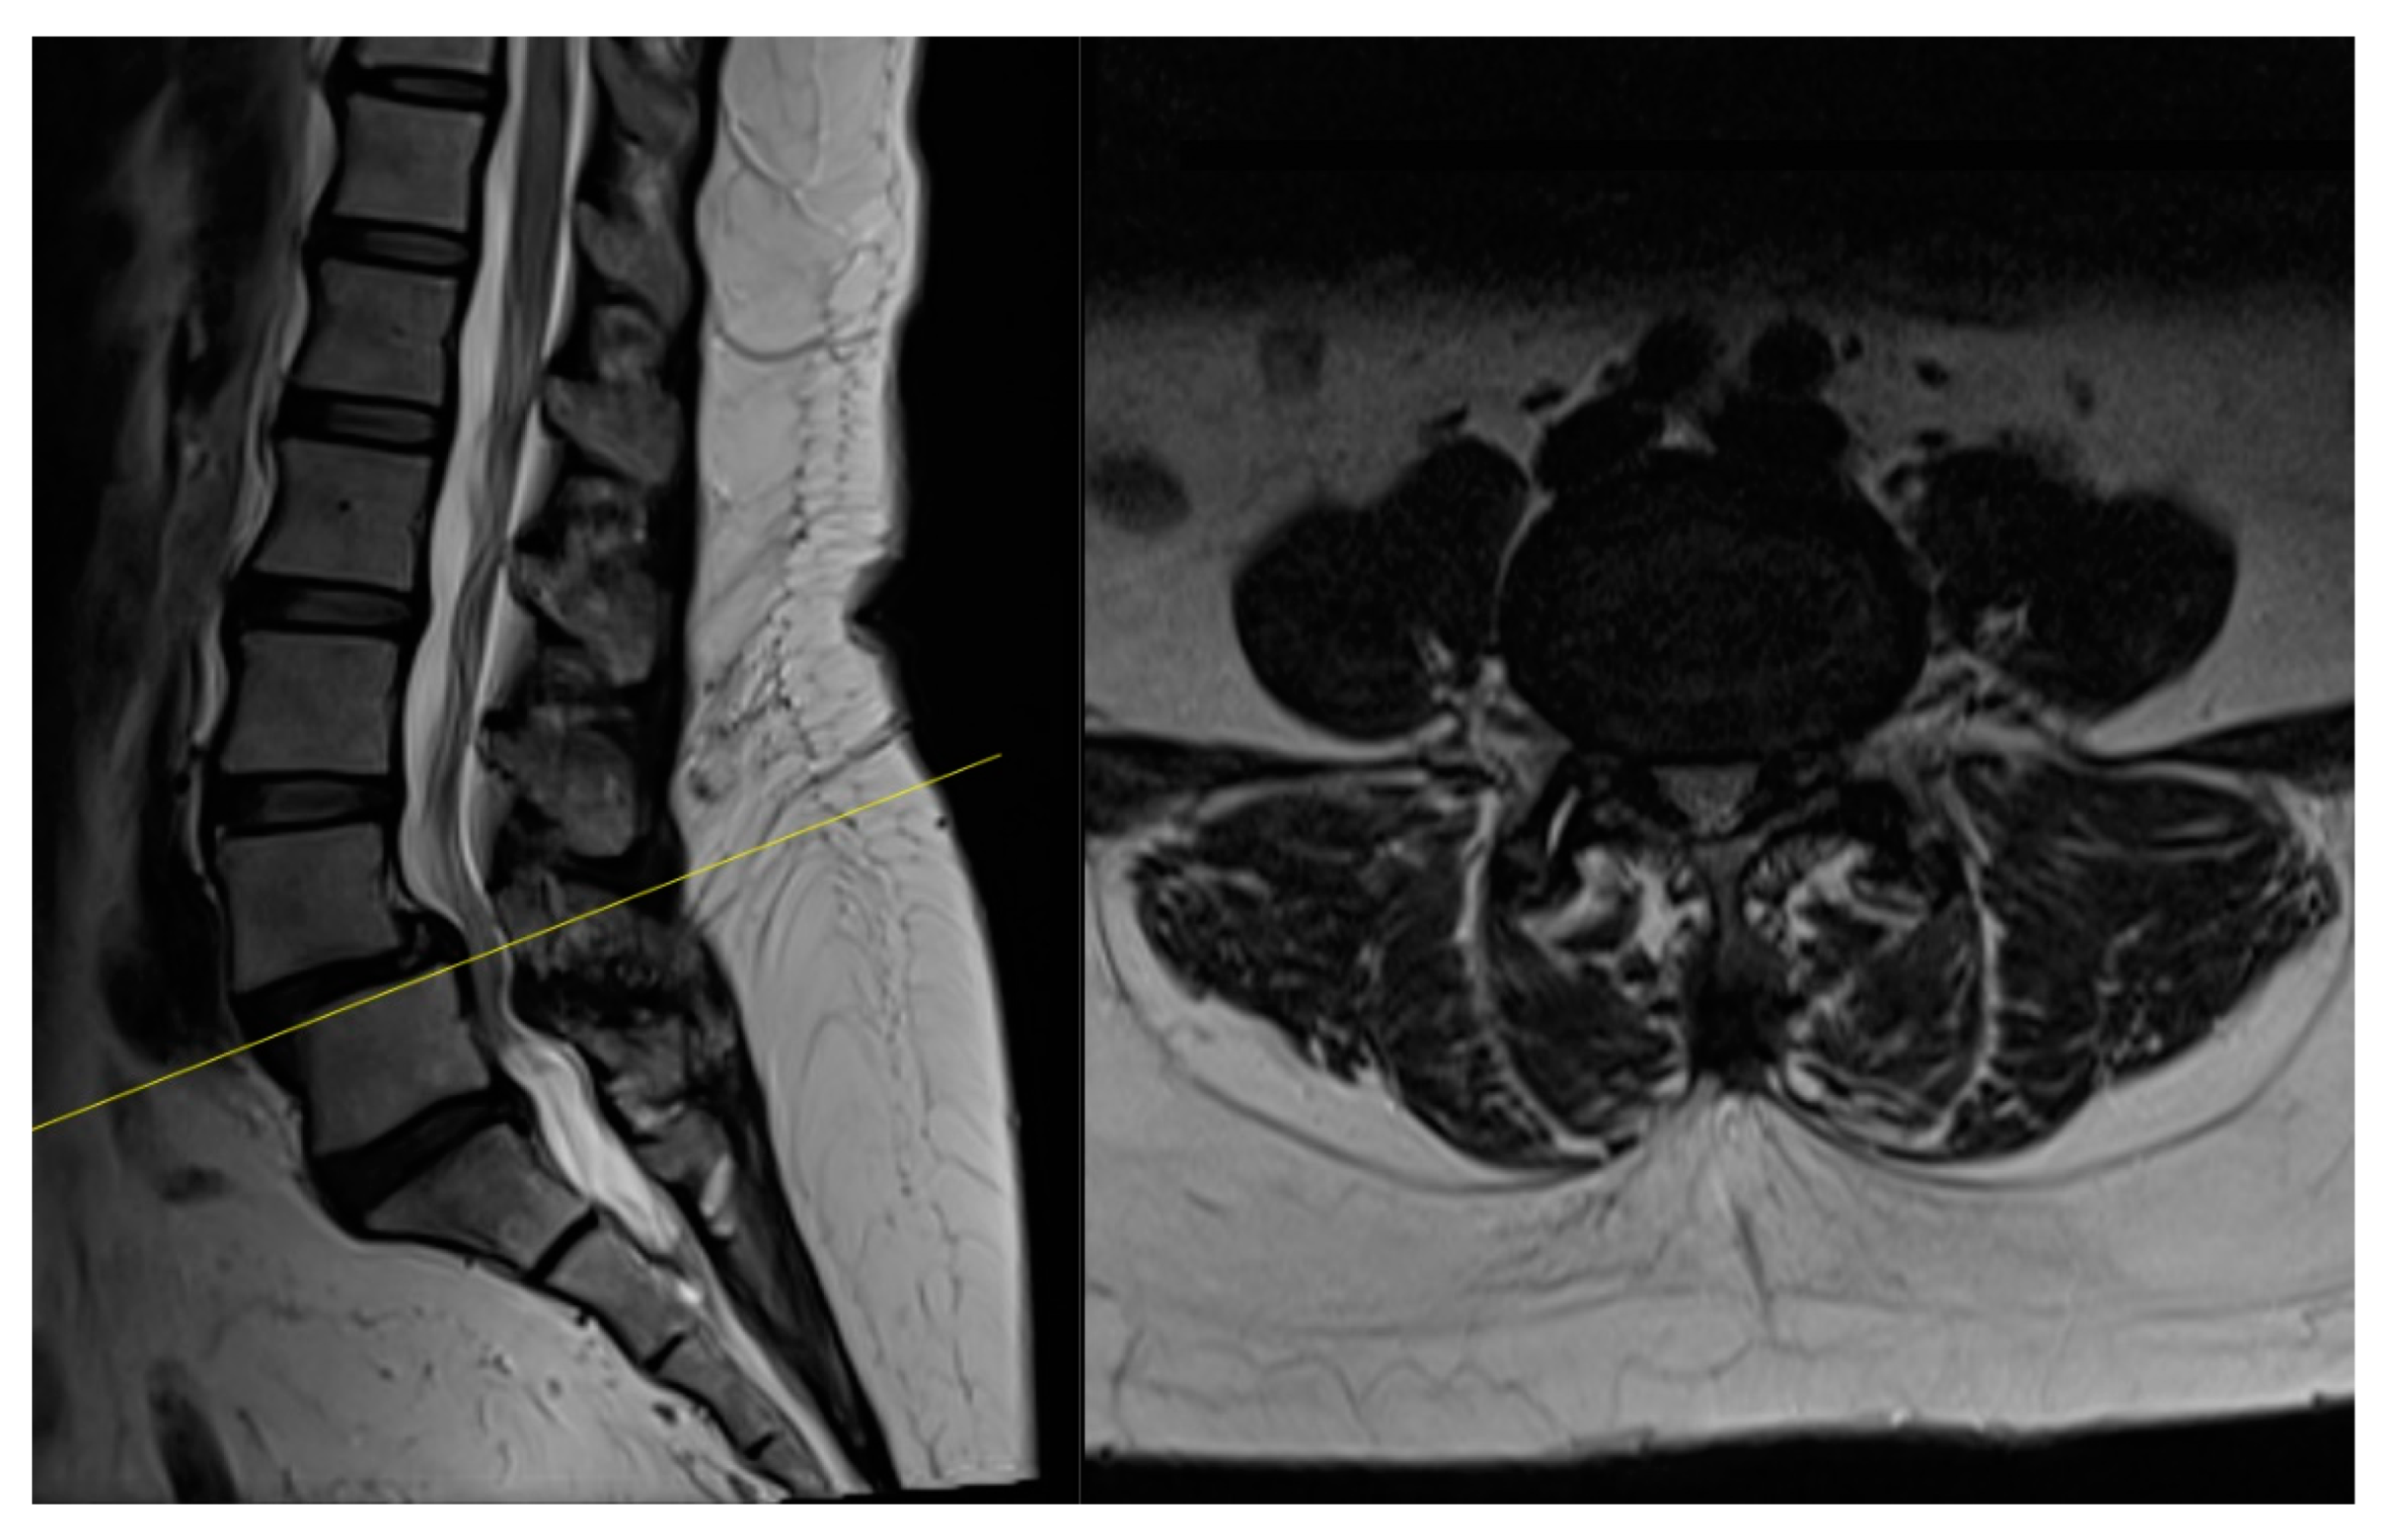

4.1. Case 1: Madam M

4.2. Case 2: Madam R

4.3. Case 3: Madam M